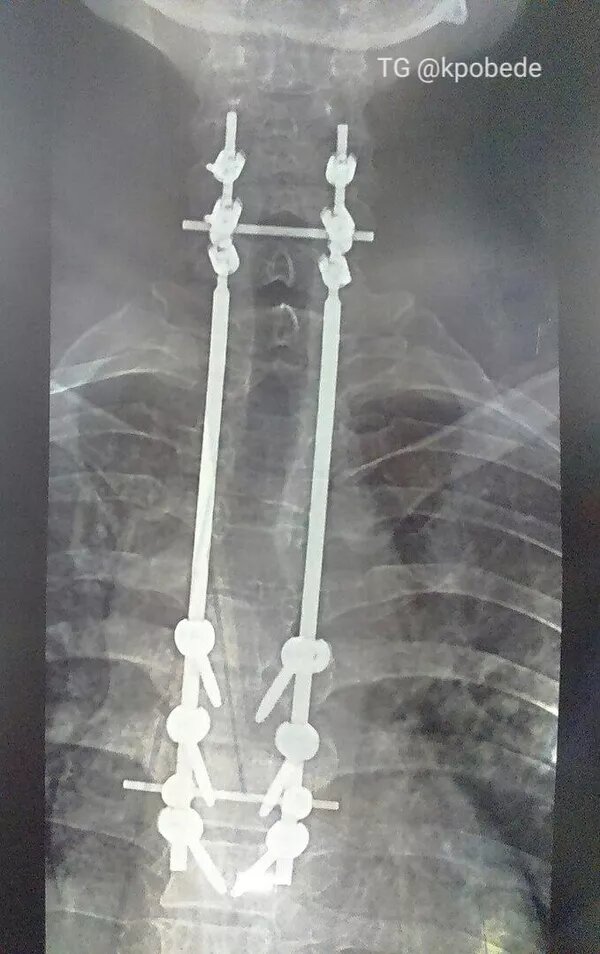

Титановая пластина добавила воинской выправки, шутит Влад. © Фото : из личного архива Влада Филина